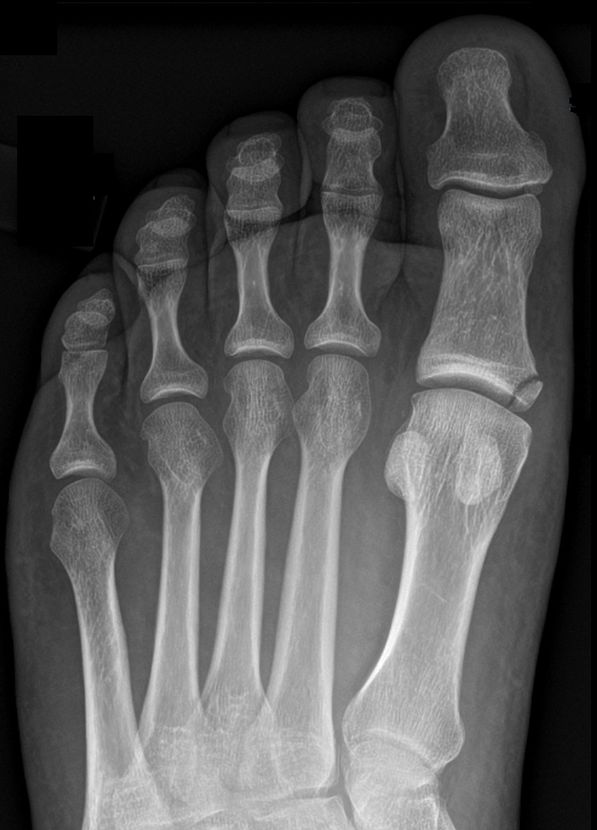

Exempel på MCL-avlösning, behandlades med hallux valgus-förband